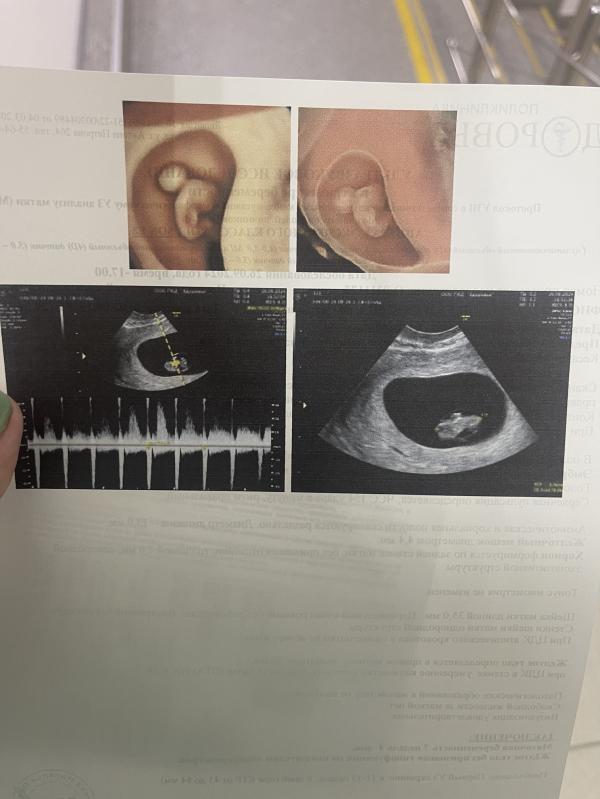

Сегодня слушала сердечко малыша, как же прекрасно, столько эмоций, не могу передать🥰

@olyapalna1, спасибо, а то я была на Гоголя Здоровья и Материнство (многими хваленые) мне даже фото не дали я даже на экране не поняла где там эмбрион, она говорит мне вот твой ребеночек ,а я только ПЯ увидела аж напугалась сначала пока сердечко не включила ))

@julia.sh, какой-то кошмар, реально, в восток меде первый раз была, там тоже распечатали, хоть даже и не видно его было, хотя клиника Здоровье и Материнство вроде в топах у нас по городу